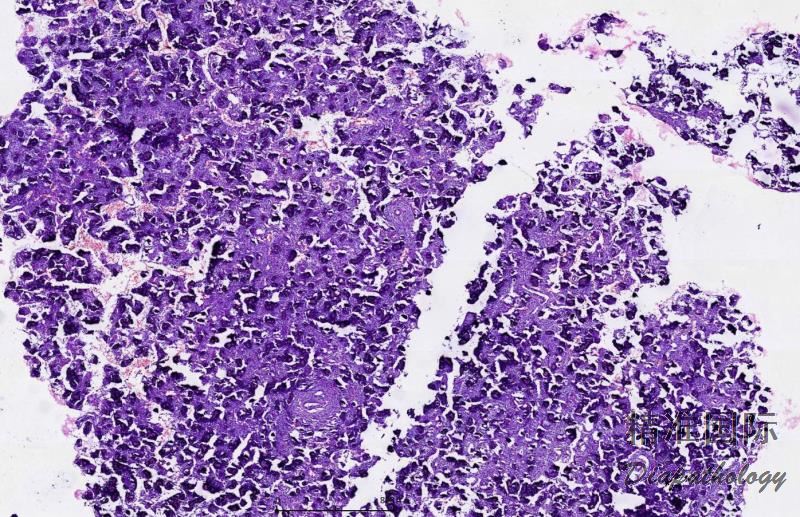

组织学中肿瘤细胞浸润性生长,包括周围软组织及骨。肿瘤细胞没有明显边界,形成脑膜上皮性(合胞体样)结节,可见漩涡状结构、沙粒体,上皮样细胞含有圆形或卵圆形核,核染色质均匀一致,核内包涵体(胞浆内陷形成)。

可见过渡型、化生型、沙粒体型及非典型脑膜瘤,但脑膜上皮瘤型脑膜瘤在鼻窦腔中最为常见。